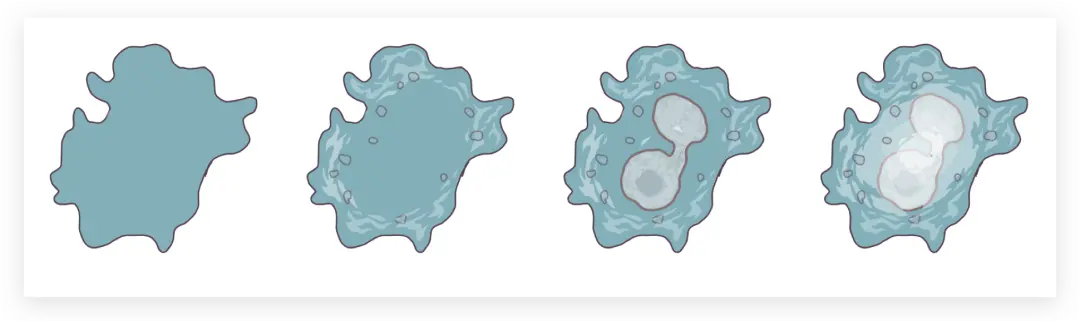

接着来画中间肿瘤细胞部分

虽然形状不同但方法一致

先用钢笔工具勾勒出外轮廓

再上色

一层层叠加图层至完成

钢笔工具画出外轮廓

上色

再复制

绿色肿瘤细胞也一样

每个形状都不一样,一个个画出来

注意明暗关系

完成整个